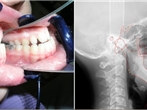

Oralna patologija, dječja stomatologija, ortodoncija, RTG dijagnostika

„Bolje spriječiti nego liječiti“ i dalje je glavni moto moderne dentalne medicine, te je naš cilj mliječne, a posebice mlade trajne zube liječiti na način maksimalne moguće poštede zdravog zubnog tkiva kako bi moglo izdržati žvačne sile cijeli život.

Pravovremene posjete doktoru dentalne medicine omogućuju ranu detekciju karijesa, parodontoloških problema i lošeg zagriza te ih je u konačnici i jednostavnije sanirati. Redovite kontrole, odstranjivanje zubnog kamenca, pravilno četkanje i održavanje zdravlja usne šupljine najbolji su ulog za budućnost.